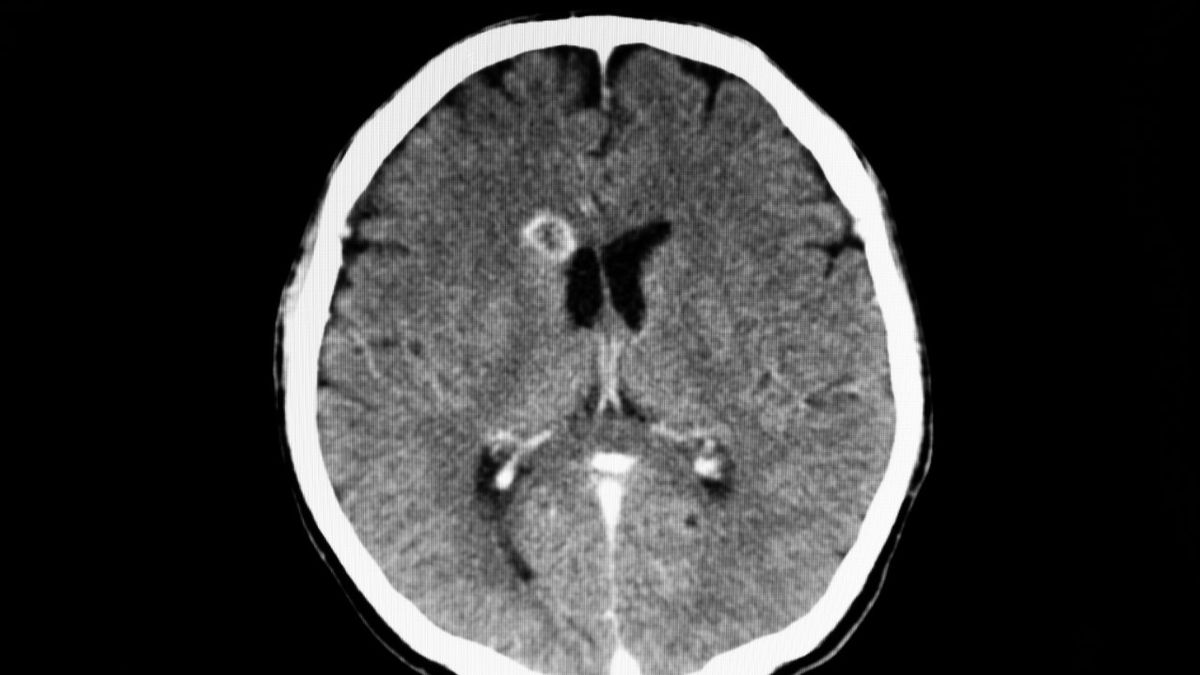

Ropień mózgu to ogniskowe zapalenie mózgu. Uznaje się, że to choroba rzadka i bardzo niebezpieczna, która grozi poważnymi powikłaniami i śmiercią. Jej przyczyną może być uraz czaszki penetrujący do mózgu, zakażenie pooperacyjne, ale i infekcja. Jakie są objawy ropnia mózgu? Na czym polega leczenie?

Ropień mózgu (łac. abscessus cerebri, ang. brain abscess) to odgraniczone zbiorowisko ropy w tkance mózgowej, które powstaje, gdy na skutek infekcji wywołanej przez bakterie, grzyby lub pierwotniaki pojawia się stan zapalny i rozpad tkanek, które w postaci płynu ulegają otorbieniu.

Podstawą rozpoznania ropnia mózgu jest badanie lekarskie i zaobserwowanie typowych objawów oraz wywiad. Diagnozę pozwalają postawić badania obrazowe mózgu: tomografia komputerowa głowy z kontrastem lub rezonans magnetyczny z kontrastem. Duże znaczenie mają badania krwi, które wykazują podwyższony poziom krwinek białych i białka C-reaktywnego (CRP) oraz wysoki odczyn Biernackiego (OB).